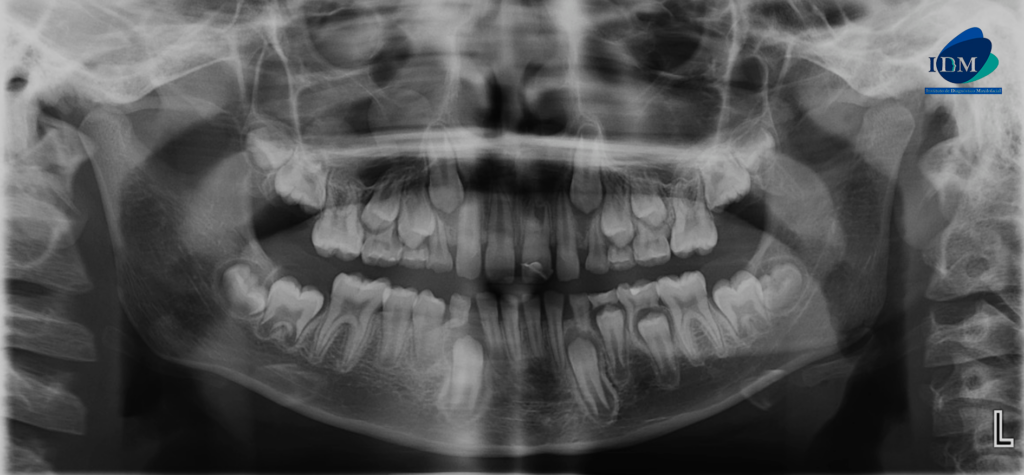

A la evaluación de la tomografía volumétrica (cone beam) de campo reducido en los cortes axiales (Figura 2) y transaxiales (Figura 3) se observa la pieza 21 con material restaurador coronal, obliteración de cámara y conducto radicular en tercio cervical y medio; además de observar la formación radicular incompleta caracterizado por tercio apical de conducto y foramen apical amplio; signos compatibles con secuela de trauma dental.

CORTES AXIALES